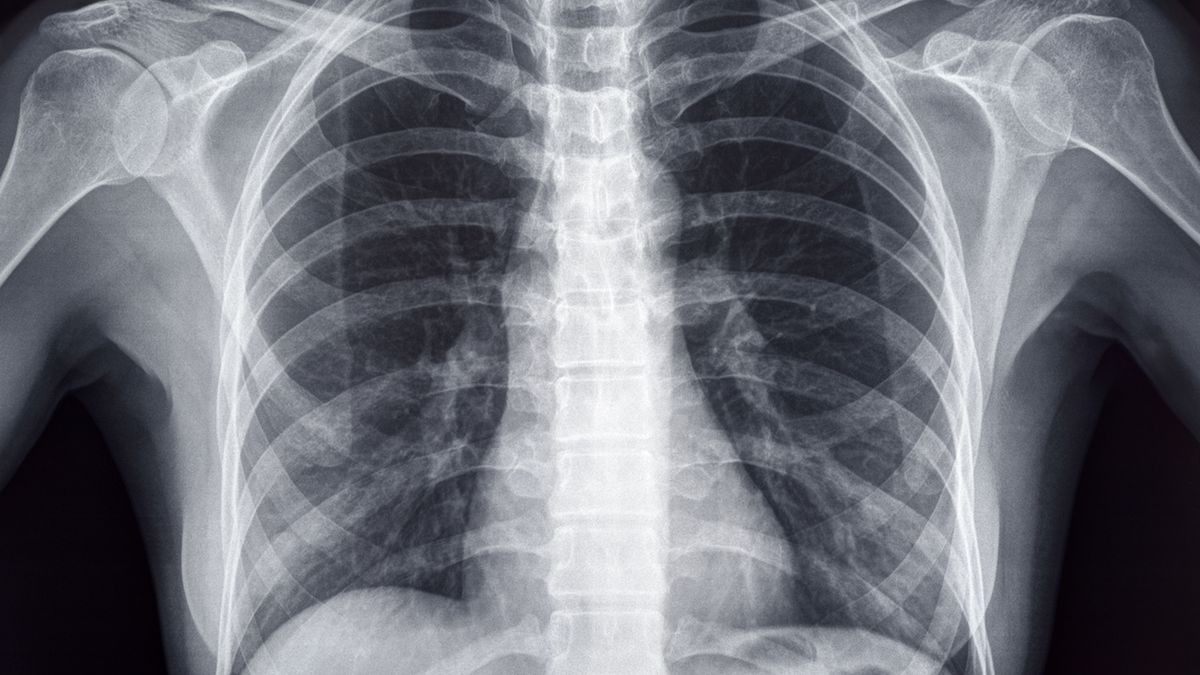

Złamanie mostka - objawy, diagnoza, leczenie

Złamanie mostka następuje głównie w wypadkach komunikacyjnych, gdy klatka piersiowa uderza o kierownicę lub w wyniku zmiażdżenia. Od kiedy jazda samochodem z zapiętymi pasami bezpieczeństwa stała się obowiązkowa, notuje się więcej przypadków tego typu urazów. Najczęściej złamaniu ulega trzon mostka, rzadko z przemieszczeniem. Jest to uraz ciężki, który może powodować uszkodzenie narządów wewnętrznych klatki piersiowej, w szczególności serca i płuc.

Złamanie mostka rozpoznaje się na podstawie zdjęcia rentgenowskiego. Niekiedy konieczna jest również tomografia komputerowa. Chorzy powinni zostać na obserwacji w szpitalu – należy bowiem upewnić się, czy nie doszło do stłuczenia serca. Złamania mostka z przemieszczeniem do śródpiersia kwalifikują się do leczenia operacyjnego, nastawienia złamania i zespolenia odłamów.